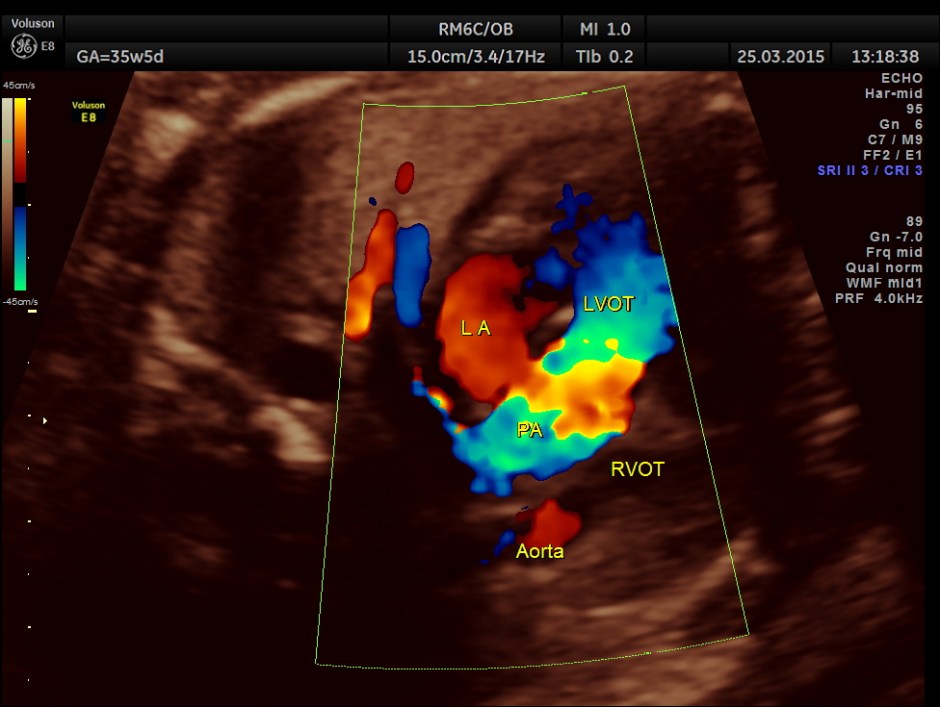

The artery coming out of left ventricle branches into two – suggestive of pulmonary artery.

The great artery arising from the LV branches into two suggestive of pulmonary artery.

The great vessel arising from the right ventricle instead of crossing runs parallel to the vessel arising from the LV.

The great artery arising from the hypoplastic right ventricle runs parallel to the artery arising from the left ventricle.